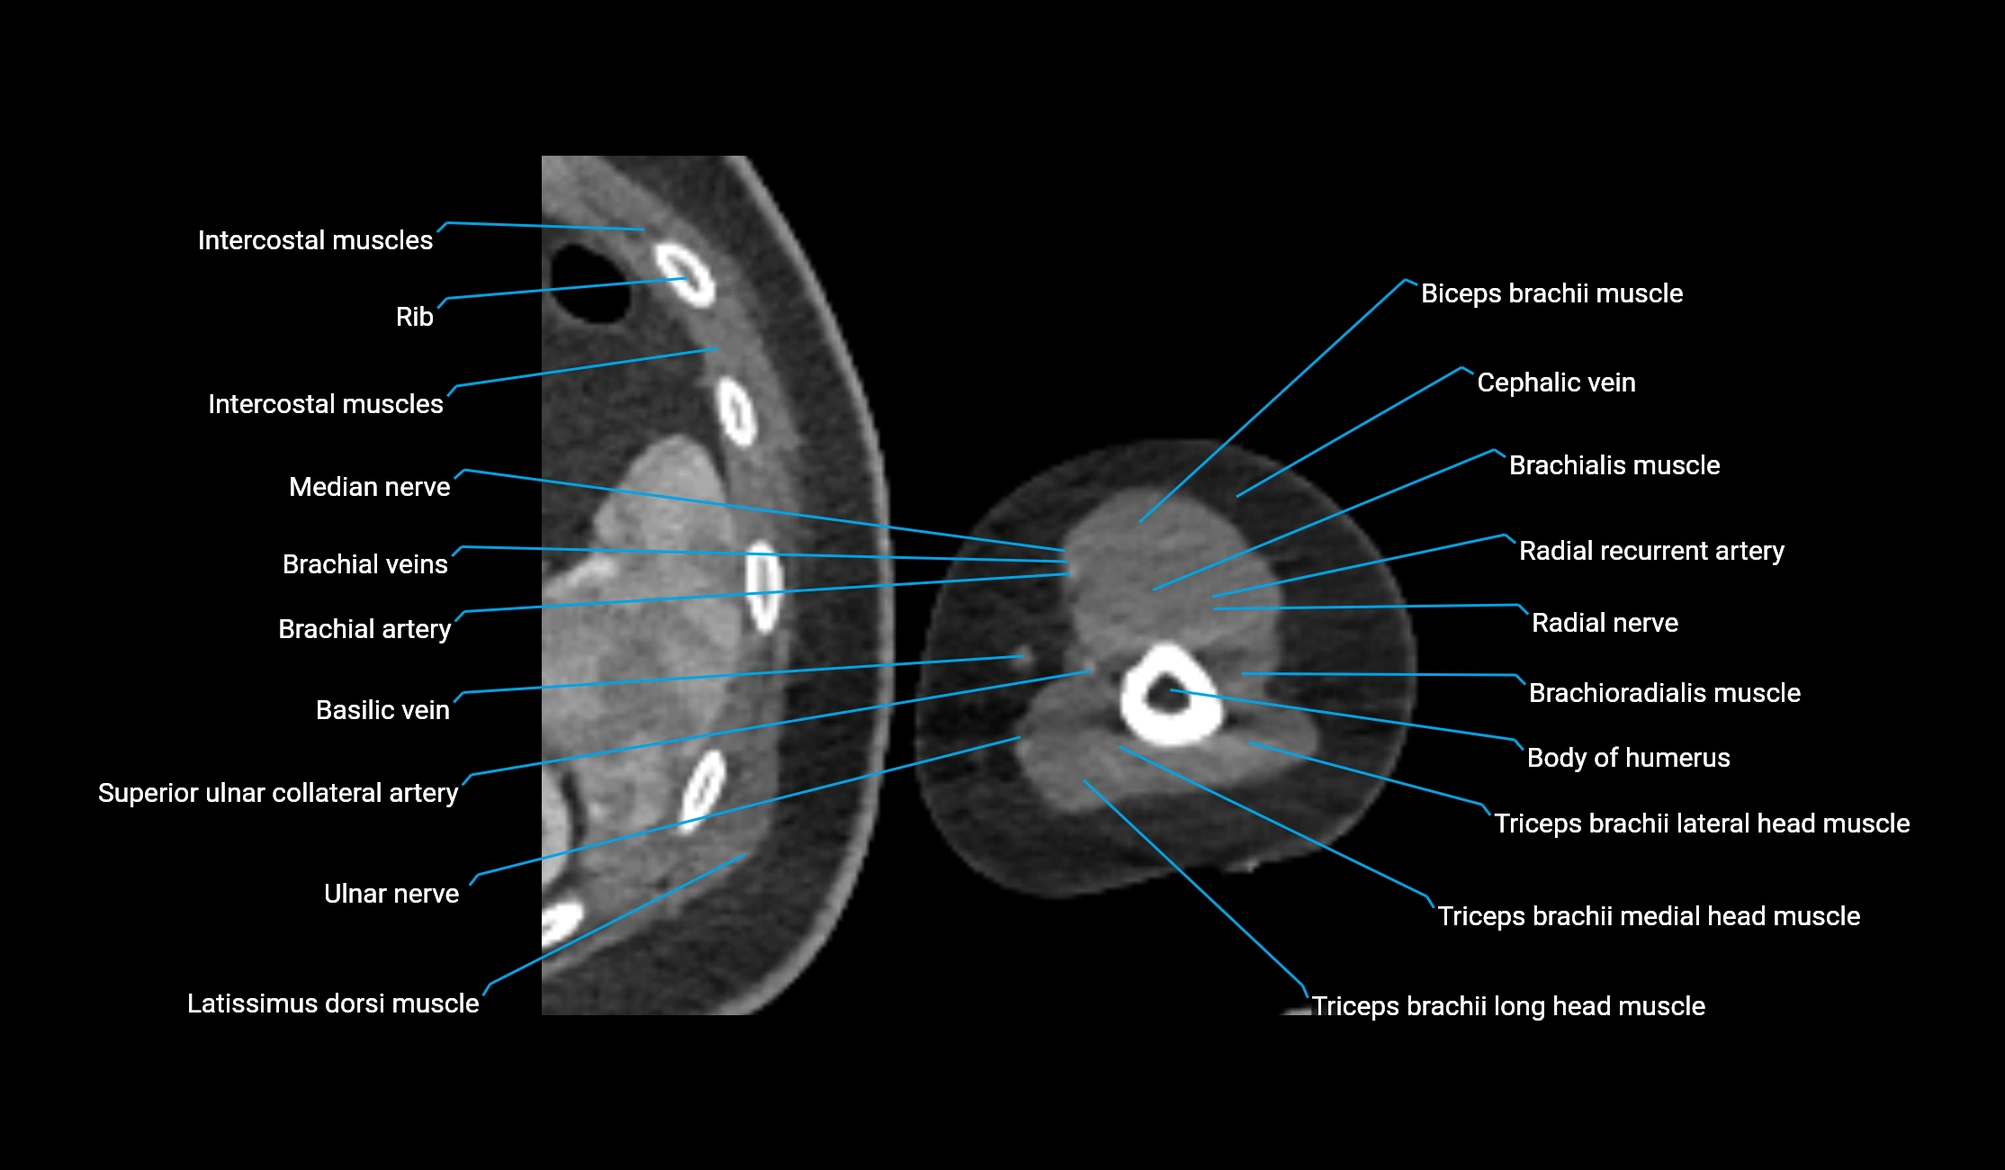

- Body of humerus

- Brachialis muscle

- Brachioradialis muscle

- Cephalic vein

- Lateral head of triceps brachii muscle

- Long head of triceps brachii muscle

- Medial head of triceps brachii muscle

- Median nerve

- Radial nerve

- Radial recurrent artery

- Superior ulnar collateral artery

- Triceps brachii muscle